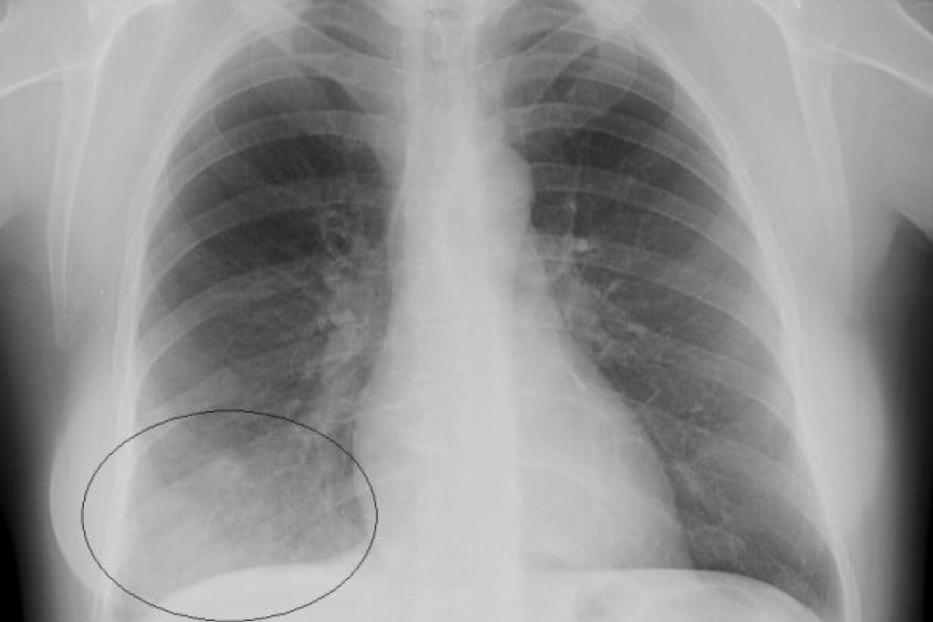

Пневмония является одной из форм острой респираторной инфекции, воздействующей на легкие. Легкие состоят из мелких мешочков, называемых альвеолами, которые при дыхании у здорового человека наполняются воздухом. При пневмонии альвеолы заполняются гноем и жидкостью, что делает дыхание болезненным и ограничивает поступление кислорода.